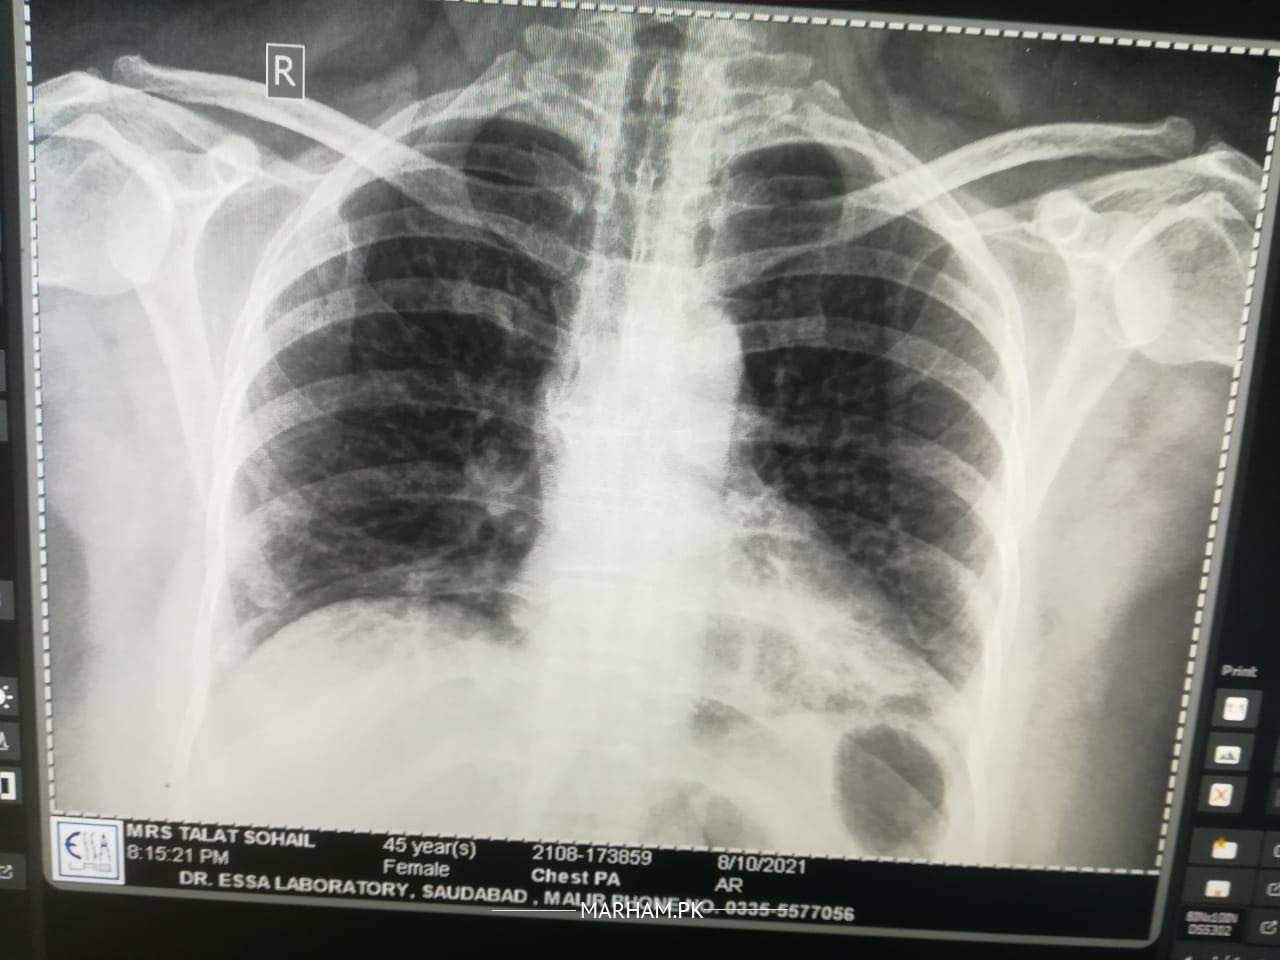

Please examine the x ray and guide is this ok xray is attached. NOTE: She had viral few days back resulting in serious cough and diagnosed with chest infection…. This xray is taken after recovery

comparison with previous x-ray required

yes chest infection

Previous xray